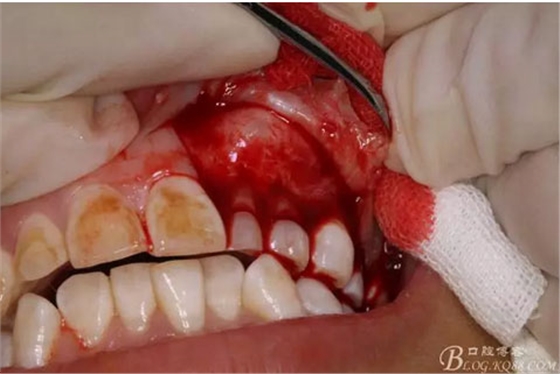

圖9.從兩個切口的連接處開始翻瓣。全厚瓣。

圖10.暴露出骨性隆起。骨質(zhì)表面光滑。

圖11.暴露出23的牙尖,牙尖垂直于唇側(cè)粘膜。建議拔除,患者同意。